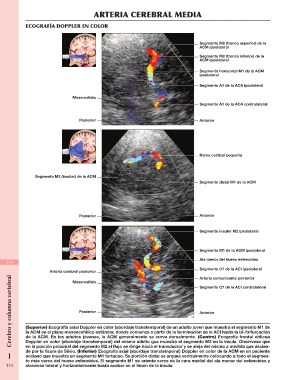

ARTERIA CEREBRAL MEDIA

ECOGRAFÍA DOPPLER EN COLOR

Mesencéfalo Segmento M2 (tronco superior) de la

Posterior ACM ipsolateral

Segmento M2 (tronco inferior) de la

ACM ipsolateral

Segmento horizontal M1 de la ACM

ipsolateral

Segmento A1 de la ACA ipsolateral

Segmento A1 de la ACA contralateral

Segmento M2 (insular) de la ACM Rama cortical pequeña

Segmento distal M1 de la ACM

114 Segmento insular M2 ipsolateral

Arteria cerebral posterior

Mesencéfalo Segmento M1 de la ACM ipsolateral

Ala menor del hueso esfenoides

Segmento C7 de la ACI ipsolateral

Arteria comunicante posterior

Segmento C7 de la ACI contralateral

(Superior) Ecografía axial Doppler en color (abordaje transtemporal) de un adulto joven que muestra el segmento M1 de

la ACM en el plano mesencefálico estándar, donde comienza a partir de la terminación de la ACI hasta la bi-/trifurcación

de la ACM. En los adultos jóvenes, la ACM generalmente se curva dorsalmente. (Centro) Ecografía frontal oblicua

Doppler en color (abordaje transtemporal) del mismo adulto que muestra el segmento M2 en la ínsula. Obsérvese que

en la porción proximal del segmento M2 el flujo se dirige hacia el transductor y se aleja del mismo a medida que ascien-

I de por la fisura de Silvio. (Inferior) Ecografía axial (abordaje transtemporal) Doppler en color de la ACM en un paciente

anciano que muestra un segmento M1 tortuoso. Su porción distal se arquea ventralmente colocando a todo el segmen-

to más cerca del hueso esfenoides. El segmento M1 se orienta cerca de la cara medial del ala menor del esfenoides y

114 atraviesa lateral y horizontalmente hasta acabar en el limen de la ínsula.